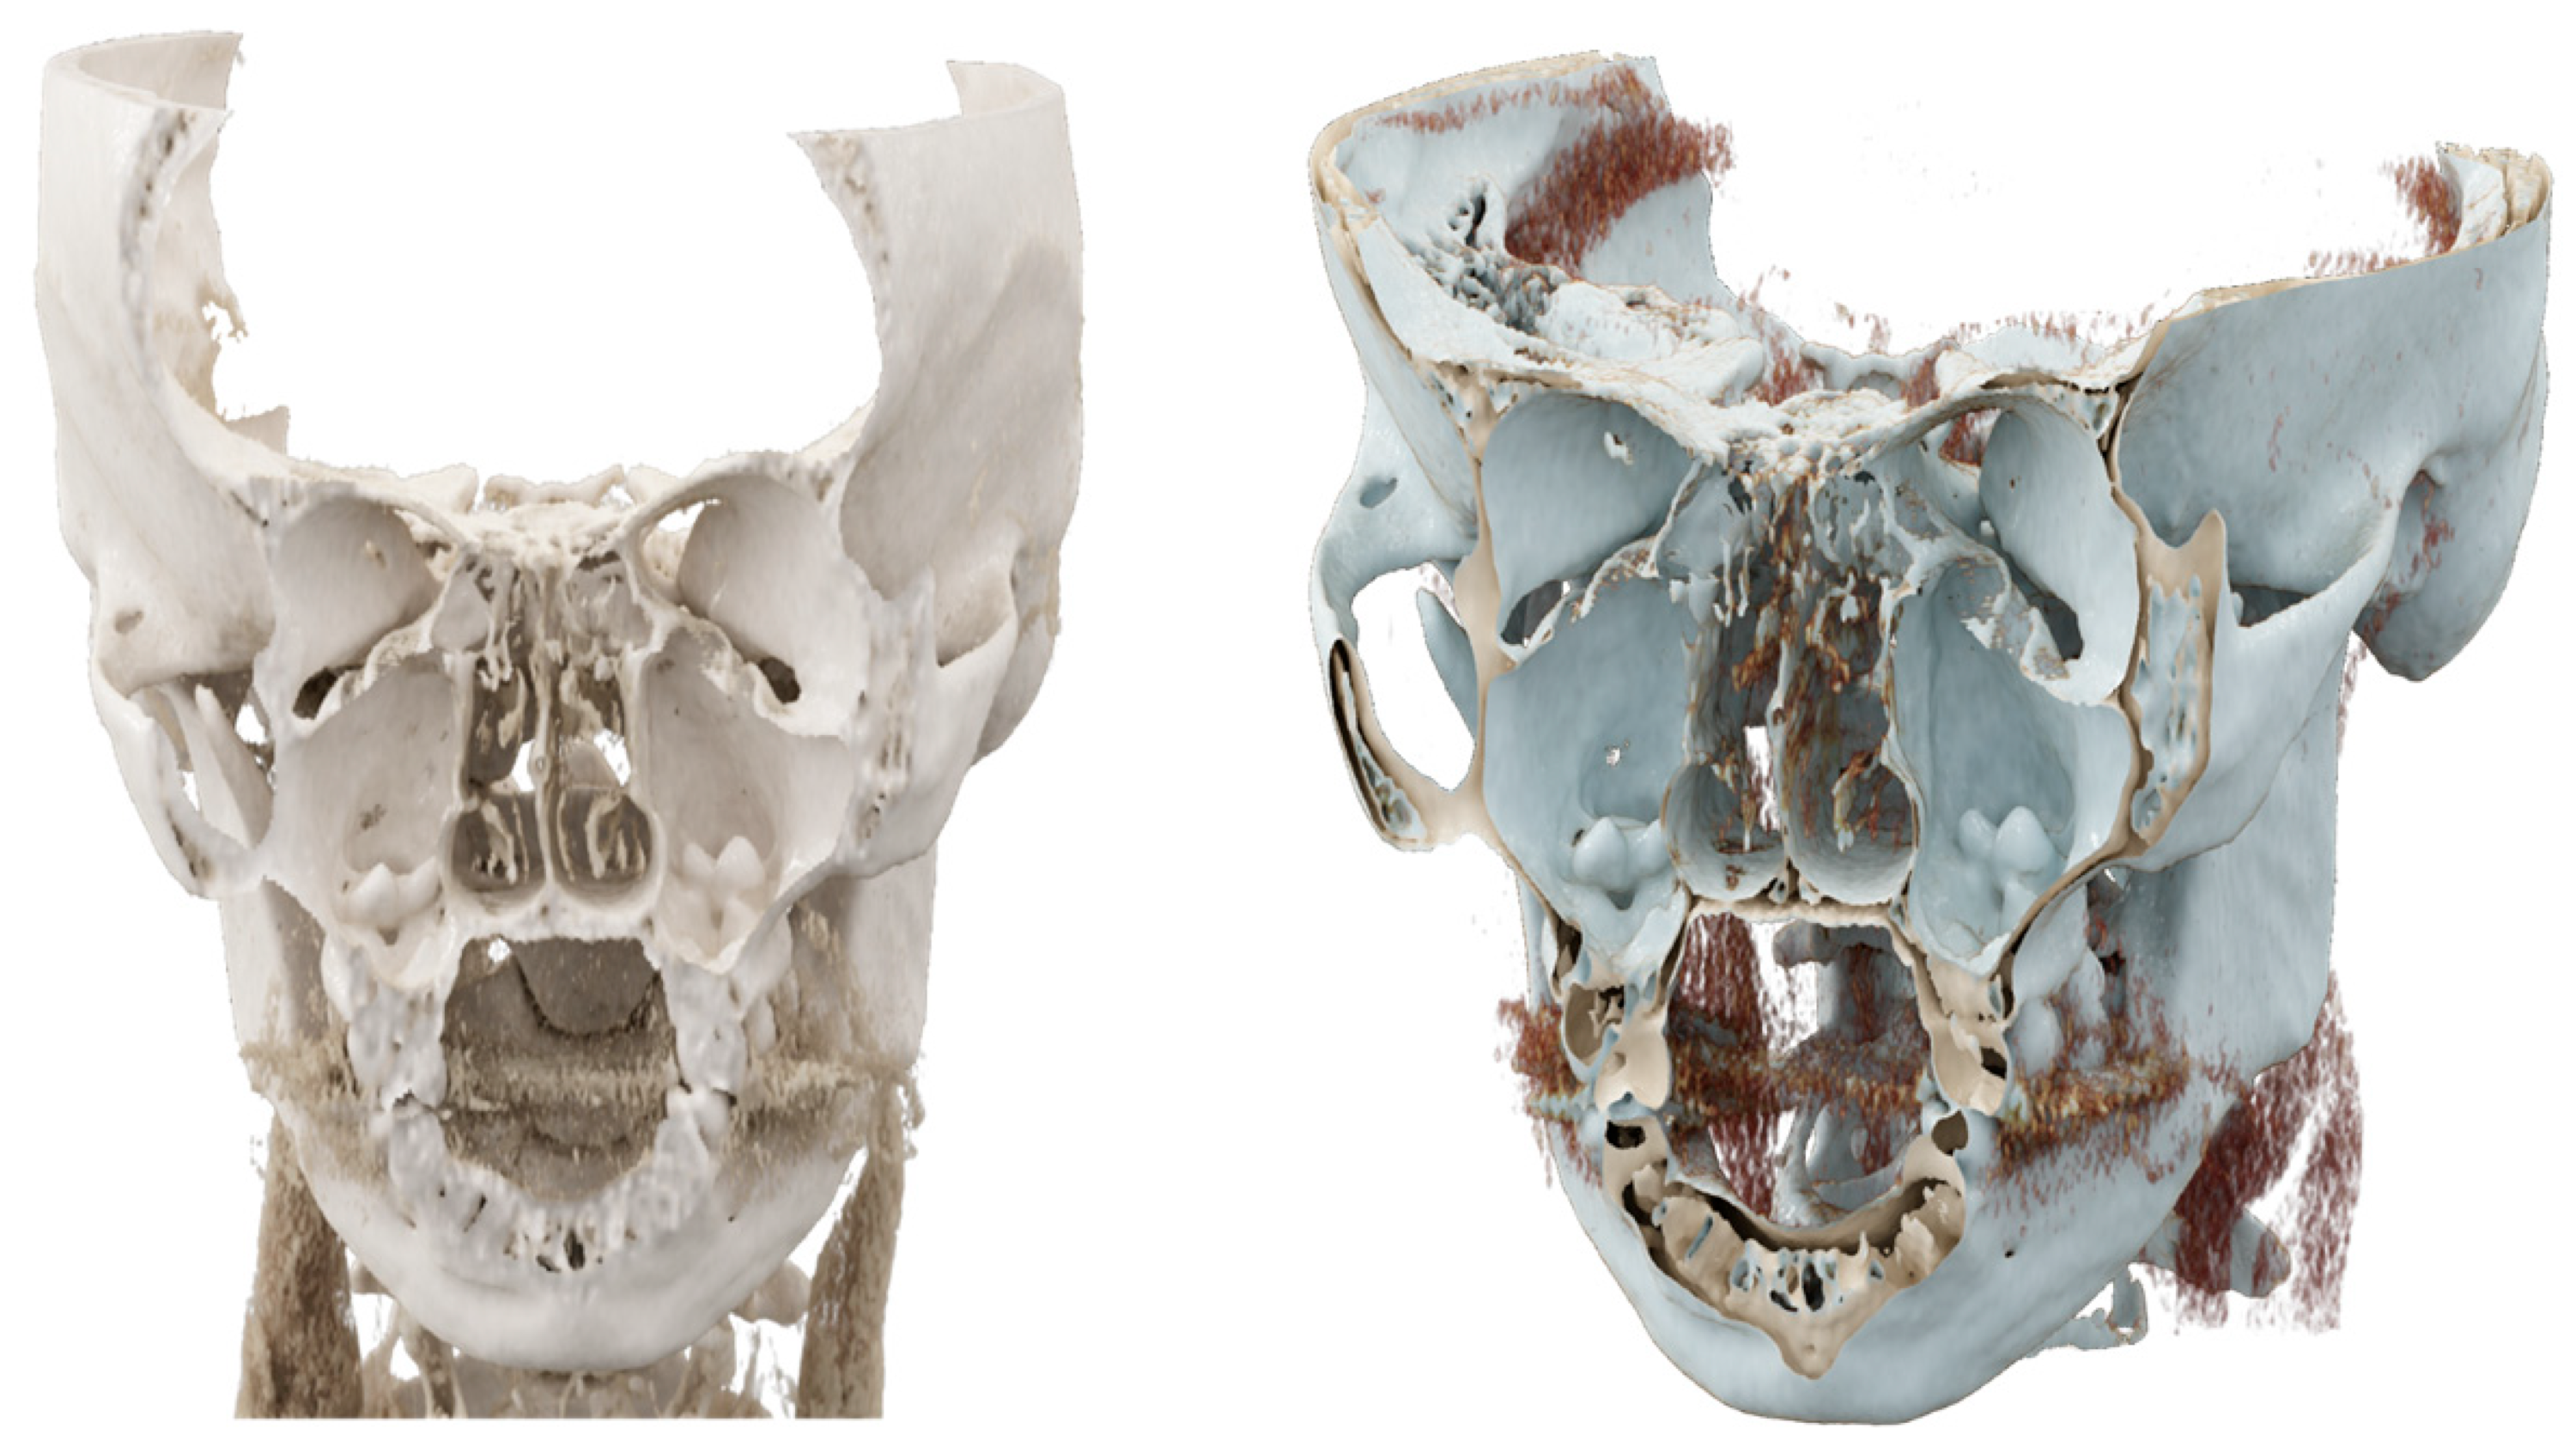

None of the reported works and cases have ever used volume rendering (VR) or CR for three-dimensional visualization of the molar in the maxillary cavity.

CT provides detailed information about the location and morphology of the ectopic tooth, as well as the evaluation of surrounding anatomical structures, facilitating treatment planning.

In the present case, CT was used to visualize the ectopic teeth in the maxillary sinus. CT has been widely used to diagnose ectopic teeth in the maxillary sinus because it can provide detailed information about the location and morphology of the ectopic tooth. In addition, CT allows evaluation of the surrounding anatomical structures, such as the sinus walls and adjacent teeth, in light of a possible surgical treatment, facilitating its planning [

We also used cinematic rendering to visualize the ectopic teeth in the maxillary sinus. By simulating the propagation and interaction of light beams as they move through the volumetric data, cinematic rendering creates a representation of 3D pictures that is more lifelike than that produced by ordinary volume rendering [

11]. In general, cinematic rendering uses the same procedures as volume rendering to determine color and opacity: transfer functions are employed to convert the gray values in each voxel of the original pictures to a color and opacity value. Afterward, a variety of transfer functions can be used for rendering, based on the case’s features and the structures that should be highlighted. However, the algorithm used in cinematic rendering is based on path-tracing techniques and the global illumination model, which simulate the various paths that billions of photons traveling from all possible directions take through a volumetric dataset and their interaction with the volume to form one pixel. This is in contrast to ray casting techniques, in which each pixel is formed by one light ray. As a result, this recently introduced 3D reconstruction technique provides more realistic 3D images with high spatial resolution and excellent tissue differentiation. Just like VR, CR can offer insights into various tissue types by adjusting the display parameters to enhance the visualization of soft tissues compared to denser structures. CR’s shadowing capabilities can enhance our understanding of anatomy, especially in areas with complex structures, including those with overlapping or protruding elements. However, it is worth noting that the prospective view in CR may partially obscure deeper regions.

In contrast to traditional VR, which treats each reconstructed voxel independently, CR presents neighboring voxels interactively. This adaptability allows for the manipulation of lighting and shadow conditions in a panoramic view. Furthermore, in addition to shadowing, CR’s global lighting model excels at revealing intricate anatomical details, making it particularly useful for visualizing small structures [

Overall, the use of CT and film rendering in our case allowed us to accurately diagnose and localize the ectopic teeth in the maxillary sinus. These imaging modalities are valuable tools in the diagnosis and management of ectopic teeth in the maxillary sinus and may aid in the planning of surgical interventions [